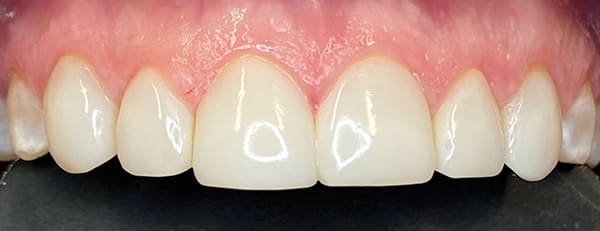

A 46-year-old female patient presented with the chief complaint of disliking the shape, color, and spacing of her front teeth. After conducting online research, the patient was adamant she did not want veneers or traditional bonding but instead preferred Bioclear® composite restorations (Bioclear, bioclearmatrix.com) on her maxillary and mandibular anterior teeth to preserve tooth structure. An intraoral scan using the iTero Element® 2 intraoral scanner (Align Technology, Inc, itero.com) and photographs were taken. It was discussed with the patient that prior to final restorations Invisalign® clear aligner therapy (Align Technology, Inc, invisalign.com) was needed to close all mandibular spacing (eliminating the need for restorations) and partially close the maxillary spacing (improving the height-to-width ratios of the final maxillary restorations). The patient completed Invisalign treatment in 15 weeks and then whitened with Opalescence™ PF 10% whitening gel (Ultradent, ultradent.com). An intraoral scan with the iTero Element 2 scanner was taken for a pre-prosthetic lab wax-up of teeth Nos. 6 through 11. These teeth were restored with full esthetic composite veneers using the Bioclear heated composite injection overmolding technique with Filtek™ Supreme Ultra Universal Restorative White Body paste and flowable (3M Oral Care, 3m.com). No tooth structure was resected. The patient was immediately scanned for Vivera® retainers. She was thrilled with her smile transformation.

Direct composite restorations with the Bioclear method

are minimally invasive, additive, and esthetically natural looking.